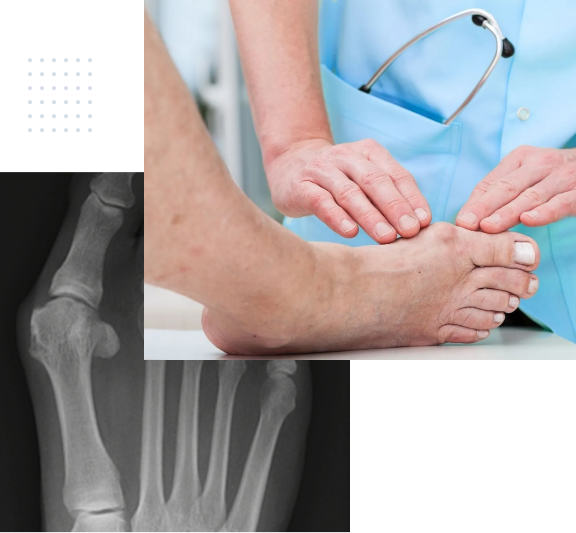

Untersuchung Hallux Valgus

Hallux Valgus

Sehr häufig werden Schmerzen im Vorfussbereich durch den Hallux valgus hervorgerufen.

Diese Deformität beschreibt eine Fehlstellung bei der der erste Mittelfussknochen nach innen, und die Grosszehe nach aussen in Richtung der anderen Zehen abweicht. Das Ergebnis ist eine sichtbare Fehlstellung der Grosszehe, die Schmerzen

verursachen kann. Das Ausmass der Deformität korreliert dabei nicht mit den Beschwerden.